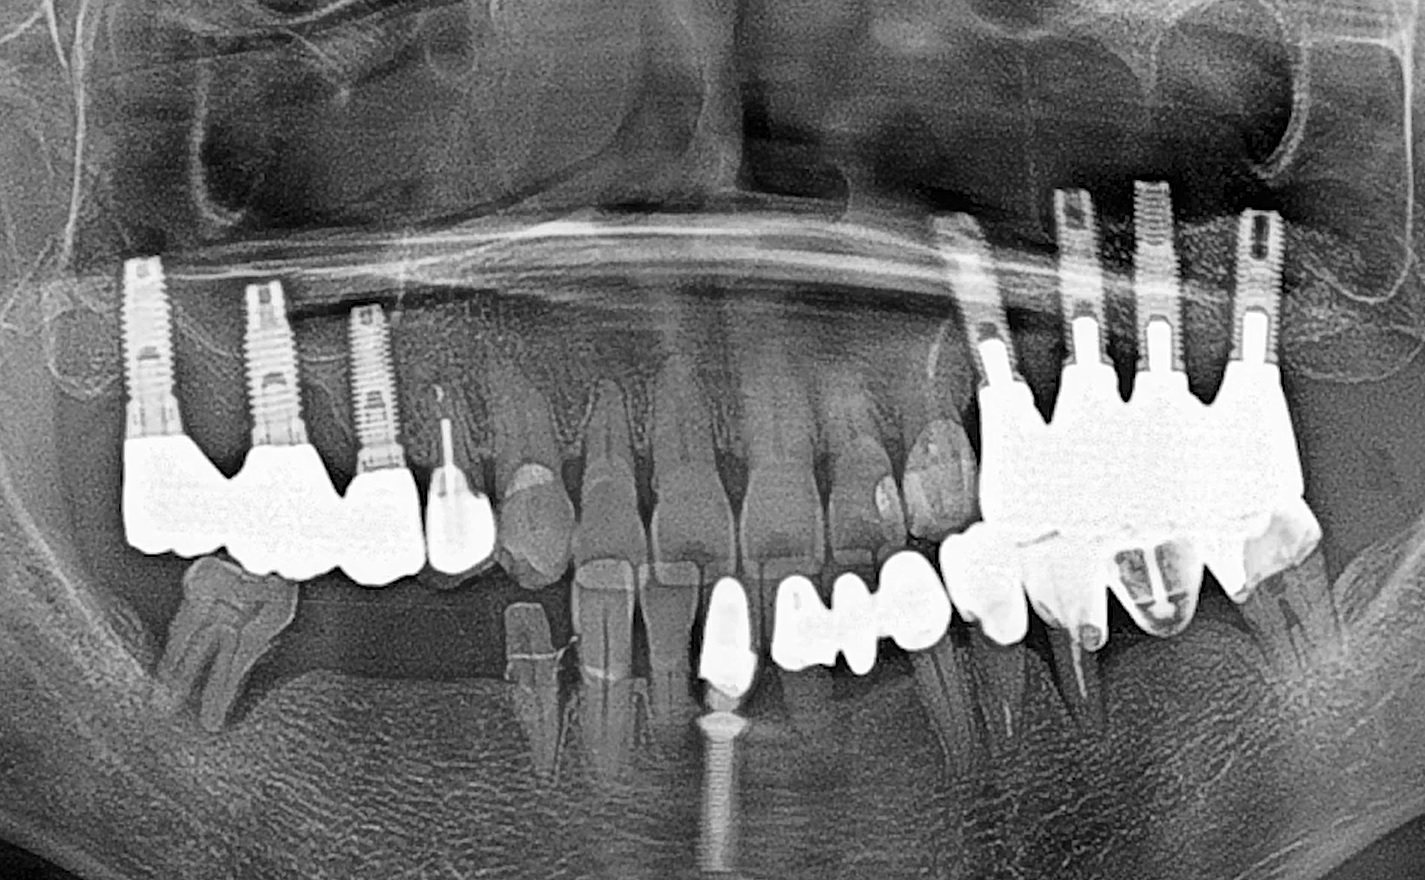

1 6 7 8